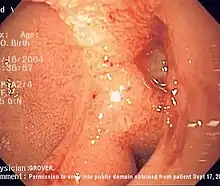

Endoscopic image of adenocarcinoma of duodenum seen in the post-bulbar duodenum.

Endoscopic image of adenocarcinoma of duodenum seen in the post-bulbar duodenum..png.webp) Endoscopic image of gastric antral vascular ectasia seen as a radial pattern around the pylorus before (top) and after (bottom) treatment with argon plasma coagulation

Endoscopic image of gastric antral vascular ectasia seen as a radial pattern around the pylorus before (top) and after (bottom) treatment with argon plasma coagulation Endoscopic image of Barrett's esophagus, which is the area of red mucosa projecting like a tongue.

Endoscopic image of Barrett's esophagus, which is the area of red mucosa projecting like a tongue. Deep gastric ulcer

Deep gastric ulcer Endoscopic still of duodenum of patient with celiac disease showing scalloping of folds.

Endoscopic still of duodenum of patient with celiac disease showing scalloping of folds.

Endoscopic image of a posterior wall duodenal ulcer with a clean base, which is a common cause of upper GI hemorrhage.

Endoscopic image of a posterior wall duodenal ulcer with a clean base, which is a common cause of upper GI hemorrhage.